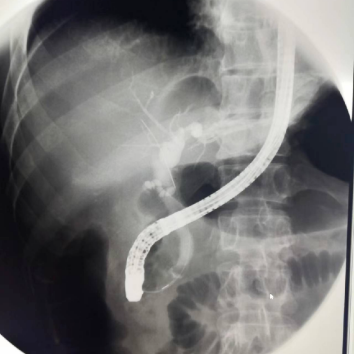

上消化道造影

數(shù)字化胃腸機可以清晰診斷食道氣管糜爛、食道靜脈曲張、食道癌、會厭綜合征、胃癌、胃竇病變、十二指腸潰瘍等病變。